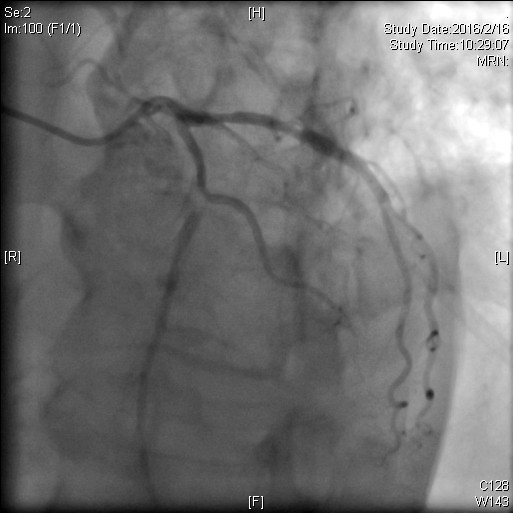

图 3 术中见冠状动脉前降支中段局限狭窄99% ,远段弥漫斑块形成

心脏内科介入团队在张萍主任领导下,反复论证,本着对生命负责的态度,决定在2016年2月16日为老人行冠状动脉介入手术,术中发现冠状动脉前降支中段几乎完全闭塞,命悬一线,依靠扎实的业务水平,术前充分的准备,缪国斌、薛亚军两位介入医生,胆大心细,顺利于前降支中段植入支架1枚,成功开通梗死相关血管,术中仅耗时40分钟,术后老人平安返回病房,继续优化药物治疗方案,很快患者的胸闷、心前区疼痛等症状好转,逐渐恢复健康,并于2016年2月23日病情稳定出院。